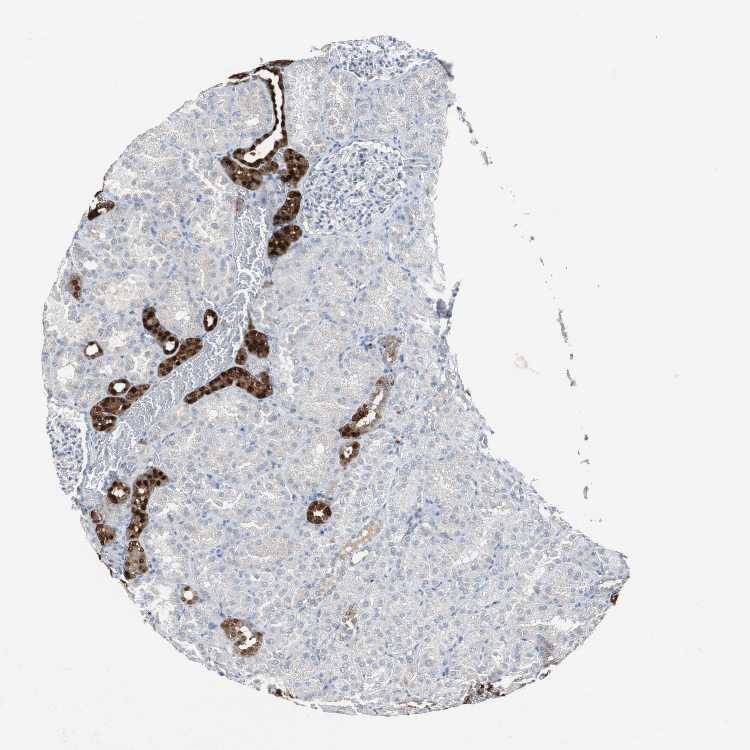

KIDNEY - Antibody stainingi

Antibody staining in the annotated cell types in the current human tissue is reported as not detected, low, medium, or high, based on conventional immunohistochemistry profiling in selected tissues. This score is based on the combination of the staining intensity and fraction of stained cells.

Each image is clickable and will lead to virtual microscopy that enables deeper exploration of all samples and also displays staining intensity scores, fraction scores and subcellular localization as well as patient and tissue information for each sample.

Antibody HPA007305Antibody HPA007306Antibody CAB000106

Cells in glomeruli Not detectedNot detectedNot detected

Cells in tubules MediumMediumNot detected